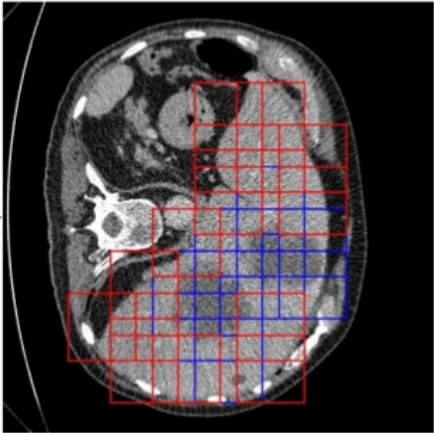

The detector works as a sliding window, placing bounding boxes over the areas where it predicts a lesion. The window is 50x50 pixels, with a margin of 15 for more context, resulting in an overall size of 80x80 pixels. As illustrated in Figure 3.8, a box is placed if it overlaps with the liver on at least a 25% area, and it is considered as positive if at least 50 pixels are considered as lesion pixels.